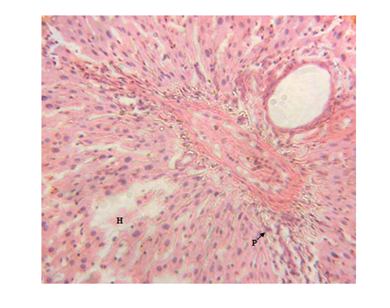

Figure 3 Liver micrograph of diabetic rat showing moderate periportal lymphocytic infiltration(P) and hepatocyte disorientation (H) at 5 weeks. (H & E stain X400).

The results of this study however disagree with the results of Jianpu et al.56 who reported that serum ALT and AST levels in diabetic rabbits were within normal ranges and Gidado et al.21 who reported insignificant changes in serum levels of ALT and AST in diabetic rats. The liver is one of the tissues that bear the brunt of chronic hyperglycaemia, since glucose is freely permeable to its cells Meyes.57 This unrestrained entry, in the presence of excess and sustained glucose in the blood is bound to cause metabolic derangements which would express themselves on the gross architecture of the tissues Atangwho et al.58 Present observations on the diabetic rat kidneys showed a progressive damage which increased with duration and severity of hyperglycemia as recorded by Muhammad et al.59 the resultant renal damage was caused by severe hyperglycemia induced by alloxan. There were septal haemorrhages, glomerular degeneration, increased capsular space with tubular epithelial damage and dysplasia as observed in kidney sections of the diabetic rats. These findings are in agreement with the findings of Kim et al.;60 Muhammad et al.;59 Renno et al.61 who showed tubular epithelial changes and enlargement of lining of cells of the tubules (Figures 5‒11).